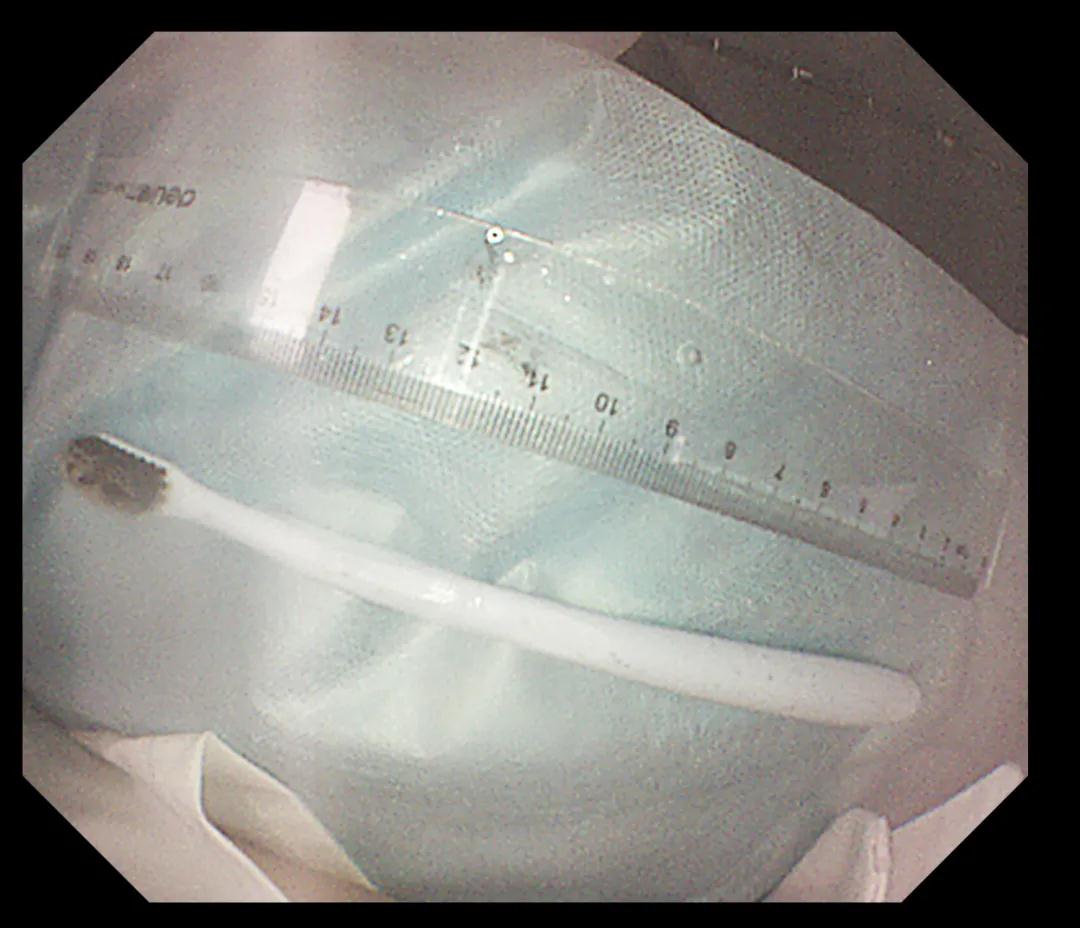

經(jīng)過反復(fù)努力嘗試,圈套器終于緊緊的套住異物,使牙刷長軸盡量與食道長軸平行,適當(dāng)注氣擴張食道腔。經(jīng)過不懈努力,順利將其取出,取出牙刷經(jīng)測量長度約20cm,似乎這條細(xì)細(xì)的胃鏡就是一條連接希望的生命線。此時在場所有人懸著的那顆心也終于落下。術(shù)后小楊癥狀逐漸消失,生命指征平穩(wěn),情緒也平靜下來。